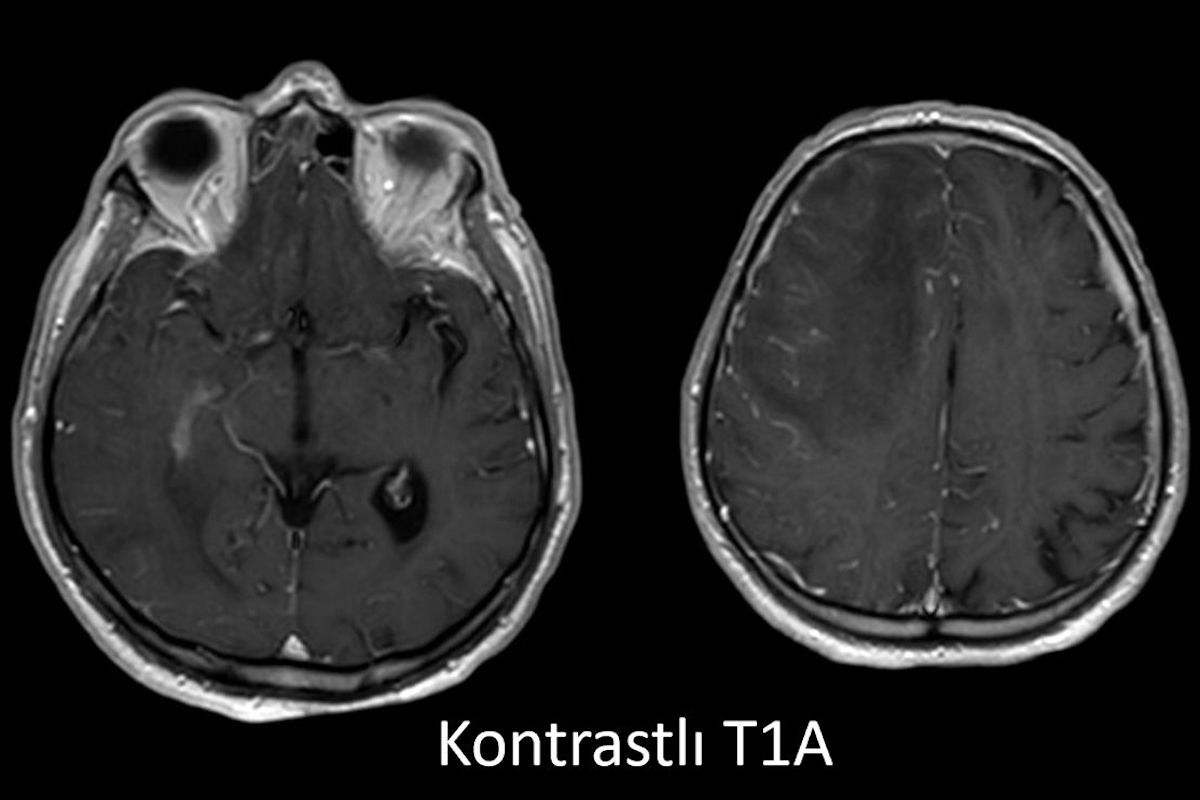

- A) Aksiyel planda FLAIR sekansta asimetrik kortiko-subkortikal vazojenik ödemi düşündüren yüksek sinyalli hafif ekspansil lezyonlar (turuncu ok).

- B) ADC haritasında kolaylaşmış difüzyon (mavi ok).

- C) Gradient seride milimetrik hemosiderin kalıntıları ve süperfisyal siderozis (kırmızı ok)

- D) Kontrastlı T1A sekansta hafif leptomeningeal boyanma (sarı ok).